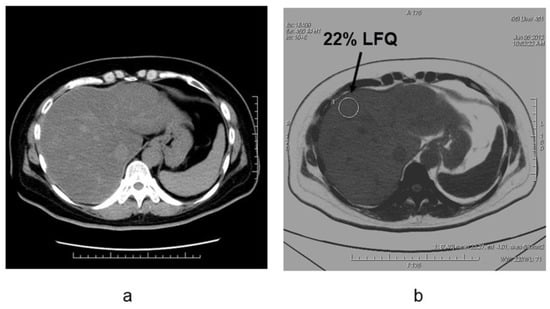

4. Evaluation of Hepatic Steatosis Using DECT

- Hyodo, T.; Yada, N.; Hori, M.; Maenishi, O.; Lamb, P.; Sasaki, K.; Onoda, M.; Kudo, M.; Mochizuki, T.; Murakami, T. Multimaterial Decomposition Algorithm for the Quantification of Liver Fat Content by Using Fast-Kilovolt-Peak Switching Dual-Energy CT: Clinical Evaluation. Radiology 2017, 283, 108–118. [Google Scholar] [CrossRef]

- Hyodo, T.; Hori, M.; Lamb, P.; Sasaki, K.; Wakayama, T.; Chiba, Y.; Mochizuki, T.; Murakami, T. Multimaterial Decomposition Algorithm for the Quantification of Liver Fat Content by Using Fast-Kilovolt-Peak Switching Dual-Energy CT: Experimental Validation. Radiology 2017, 282, 381–389. [Google Scholar] [CrossRef]

- Hur, B.Y.; Lee, J.M.; Hyunsik, W.; Lee, K.B.; Joo, I.; Han, J.K.; Choi, B.I. Quantification of the fat fraction in the liver using dual-energy computed tomography and multimaterial decomposition. J. Comput. Assist Tomogr. 2014, 38, 845–852. [Google Scholar] [CrossRef]